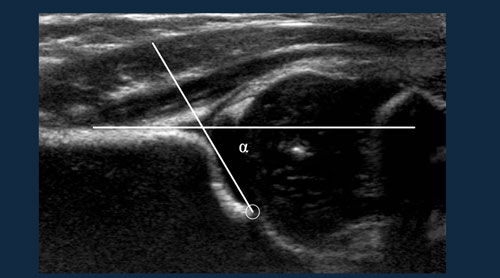

Femoroacetabular impingement syndrome

Femoroacetabular impingement

new